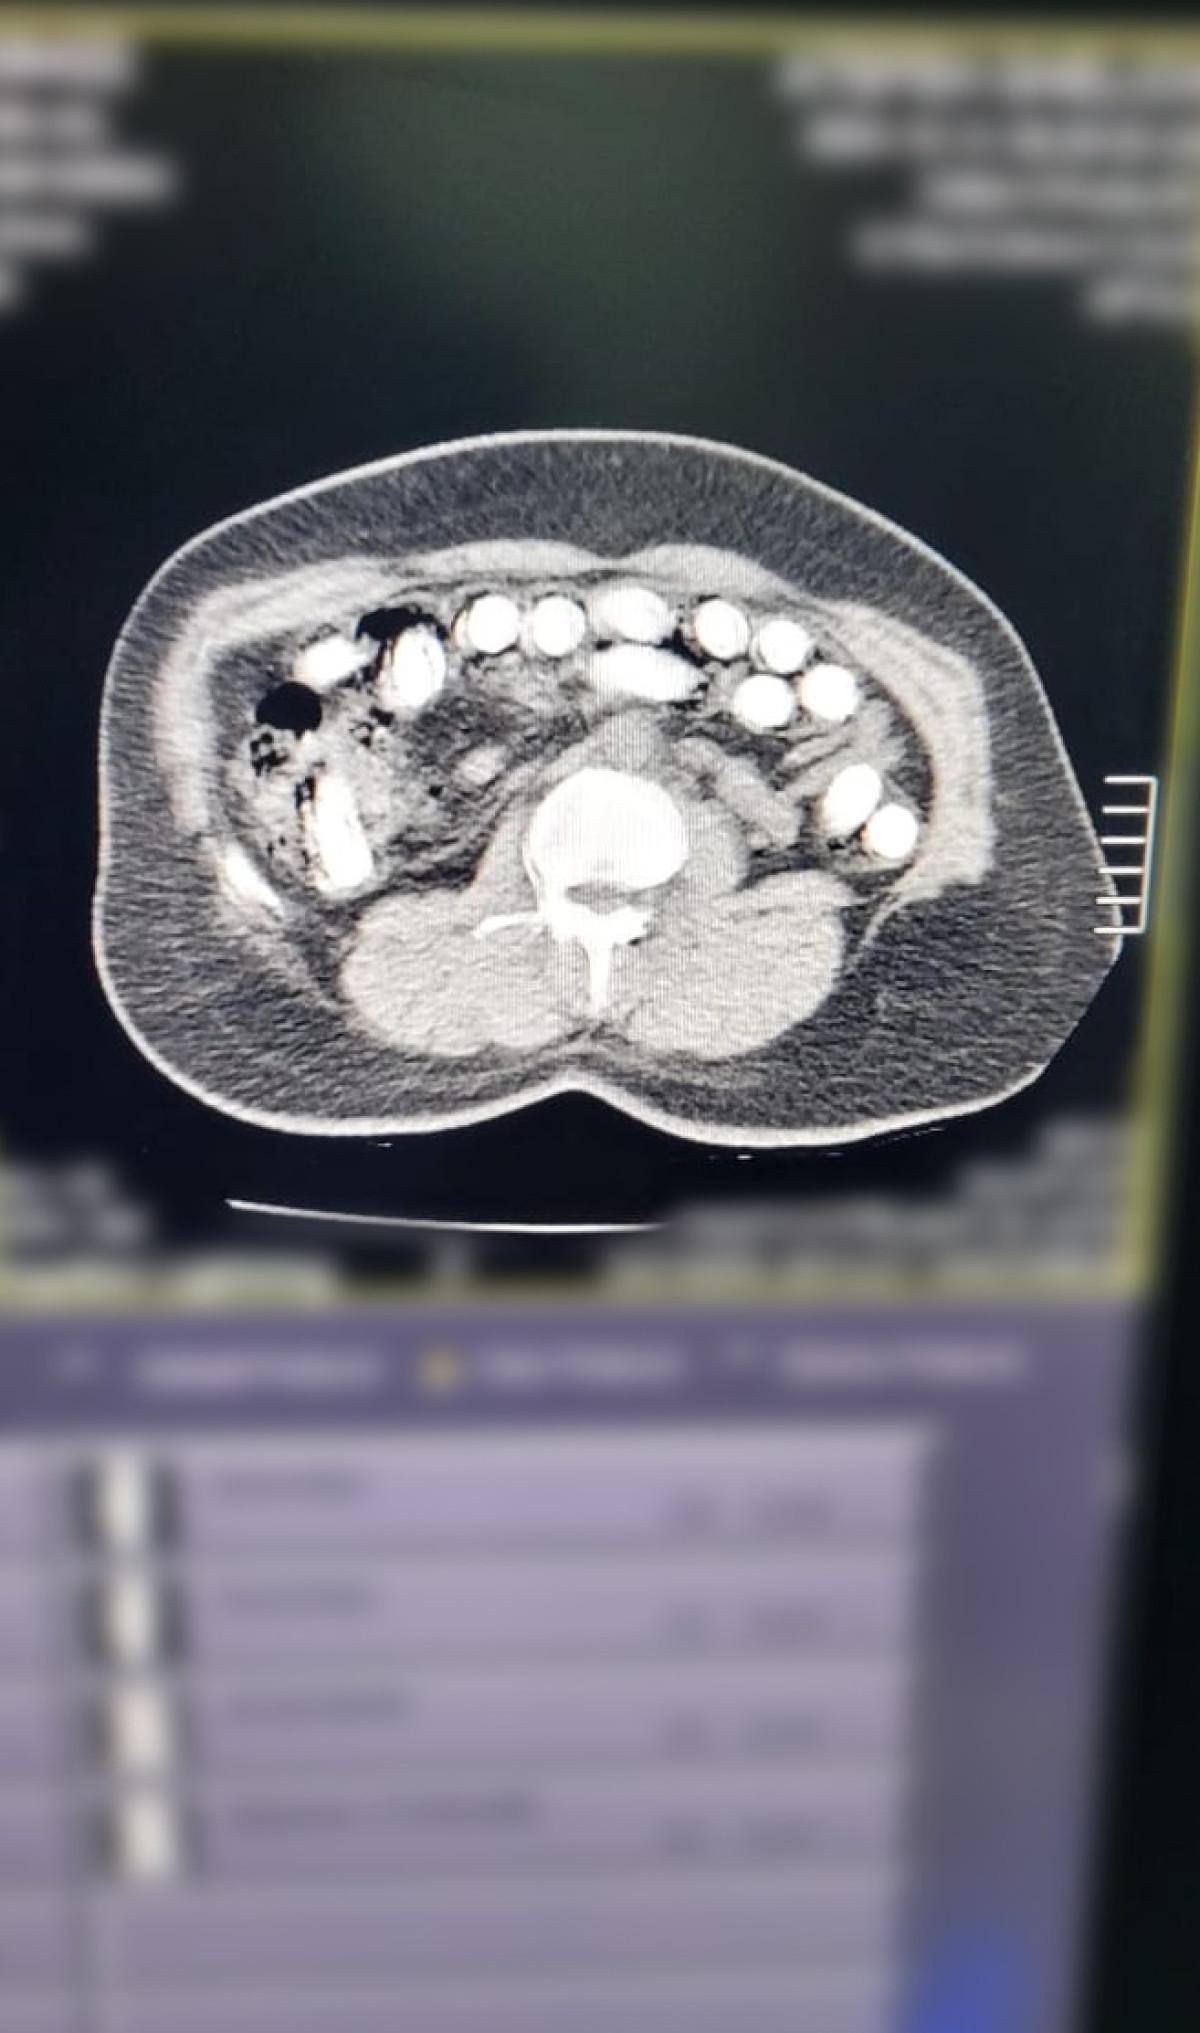

Gözaltına alınan A.G.'nin röntgen ve tomografi görüntülerinde midesinde uyuşturucu bulunduğu belirlendi. Gerçekleştirilen ameliyat sonucunda, şüphelinin midesinden 88 kapsül halinde toplam 974,52 gram afyon sakızı çıkarıldı. A.G., taburcu edildikten sonra her iki şüpheli "uyuşturucu madde ticareti" suçlamasıyla mahkemeye sevk edilerek tutuklandı.